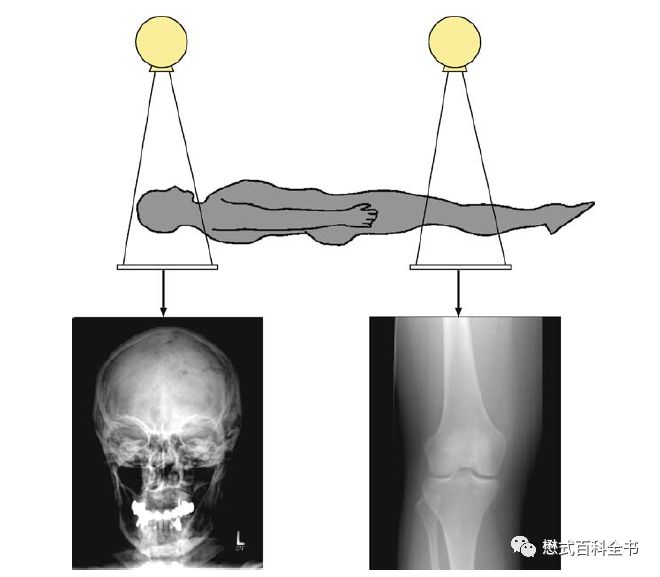

图6:传统的X线成像